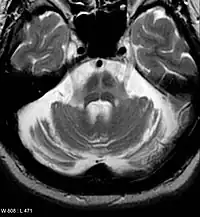

Imaging

Diagnosis can be aided by molecular imaging techniques such as magnetic resonance imaging (MRI), positron emission tomography (PET), and single-photon emission computed tomography (SPECT).[142] As both conventional MRI and computed tomography (CT) scans are usually normal in patients with early PD, they can be used to exclude other pathologies that cause parkinsonism.[141][143] Diffusion MRI can differentiate PD from multiple systems atrophy (MSA).[144] Emerging MRI techniques of at least 3.0 T field strength—including neuromelanin-MRI, 1H-MRSI, and resting state fMRI—may detect abnormalities in the substantia nigra, nigrostriatal pathway, and elsewhere.[141]

Unlike MRI, PET and SPECT use radioisotopes for imaging.[145] Both techniques can aid diagnosis by characterizing PD-associated alterations in the metabolism and transport of dopamine in the basal ganglia.[146][147] Largely used outside the United States, iodine-123-meta-iodobenzylguanidine myocardial scintigraphy can assess heart muscle denervation to support a PD diagnosis.[148]